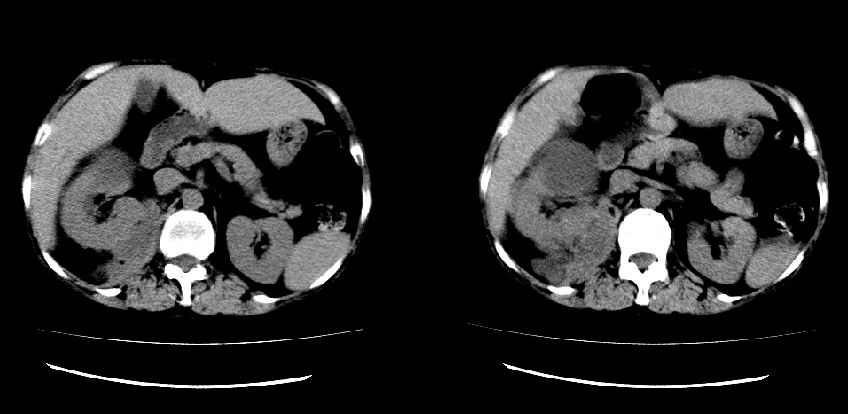

以下是引用liuyue在2008-7-19 10:17:00的发言:[br]考虑:1.肾周脓肿,肾实质、腰大肌及侧腹壁均受累及。 2.右肾囊肿。[br]建议:强化扫描,除外肾癌之可能。[br]

以下是引用zhengfaming在2008-7-19 14:48:00的发言:[br]右肾脓肿并感染可能性大,建议增强

以下是引用江广1996在2008-7-19 10:48:00的发言:[br]先考虑右侧肾周感染脓肿形成并累及腰大肌,右肾前侧有病灶考虑囊肿。